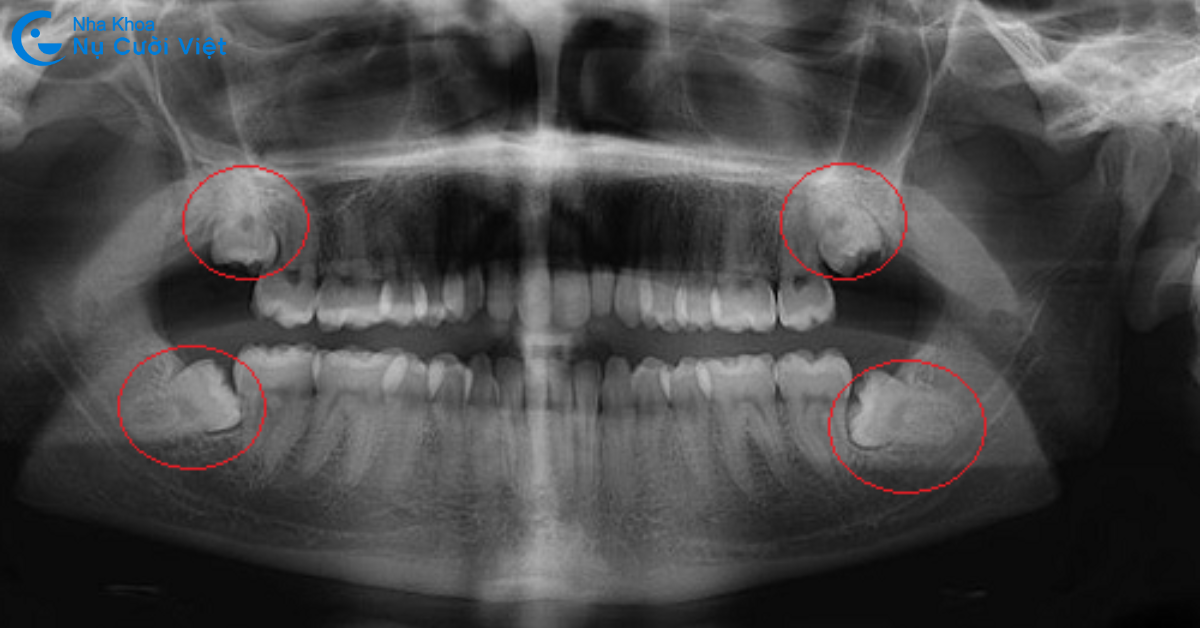

Răng khôn (răng số 8) là các răng hàm xuất hiện cuối cùng khi bạn đến độ tuổi 17 - 25. Chiếc răng này có thể mọc trước, mọc trong hoặc mọc sau quá trình niềng răng. Tùy vào trường hợp răng khôn có ảnh hưởng gì đến phác đồ niềng răng hay không mà bác sĩ có thể chỉ định khác nhau. Cụ thể, dưới đây là những trường hợp cần phải nhổ răng khôn khi niềng răng:

Răng khôn mọc lệch, nằm ngang hoặc đâm vào răng bên cạnh

Nếu răng khôn mọc lệch, hướng vào má hoặc răng số 7, đặc biệt là mọc ngang 90 độ, việc nhổ là cần thiết. Răng khôn trong trường hợp này có thể gây áp lực lên răng kế cận, dẫn đến đau nhức, viêm nướu hoặc sâu răng số 7. Ngoài ra, lực kéo của mắc cài hoặc khay niềng sẽ bị cản trở, khiến hiệu quả điều trị giảm và thời gian niềng kéo dài hơn.

Nhổ răng khôn tạo thêm khoảng trống cho việc dịch chuyển răng

Trong những trường hợp răng khấp khểnh, lệch lạc nặng, dù răng khôn mọc thẳng và không gây đau, bác sĩ vẫn có thể khuyến nghị nhổ. Lý do là răng khôn chiếm một phần không gian khá lớn ở cuối hàm, khiến việc kéo nhóm răng sau lùi vào gặp khó khăn.

Chụp X quang răng kỹ lưỡng: Bác sĩ sẽ thăm khám kỹ lưỡng, chụp X-quang cẩn thận để làm căn cứ đánh giá cấu trúc và tình trạng răng miệng của khách hàng.